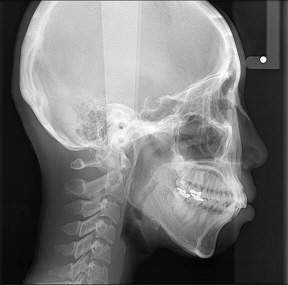

사진첨부합니다... 누가봐도 입이 나왔어요..ㅠㅠ

네...앞니의 위치에 의하여 돌출입이 생기게 된답니다. 덧니가 생기는 대신 앞니가 밀려 나와 있는 것이지요. 따라서 발치를 해야만 전체적인 치아의 위치와 치열을 맞출수 있답니다. 치료의 난이도에 영향을 주는 것은 앞니의 초기 각도인데요. 님의 경우도 쉽진 않답니다. 다만 잇몸부위의 돌출이 엑스레이 사진 상으로는 그리 심한 편은 아니라서 치아교정을 생각할 수도 있을 것 같습니다. 킬본 교정은 드러난 치아의 부위뿐 아니라 잇몸뼈안의 뿌리부분이 동반되어 돌출된 경우 이를 효과적으로 개선하기 위한 장치랍니다, 일단 명칭은 저희가 붙인 것이구요. 치아의 기울임을 최소화하면서 이동을 도모하기 좋은 장치이지요. 님과 같은 상태에 효과적이랍니다. 어금니 부위의 돌출된 뼈는 교정치료하는데 그리 걱정하진 않아도 될 것 같습니다. 치료를 하다보면 두꺼운 잇몸뼈의 모양을 갖는 분들이 치아의 이동이 좀 더딘면은 있지만 무리가 가거나 치료에 큰 영향을 주진 않는 것 같습니다. 고민이 많이 되시겠는데요. 잘 치료하시길 바랍니다....^^